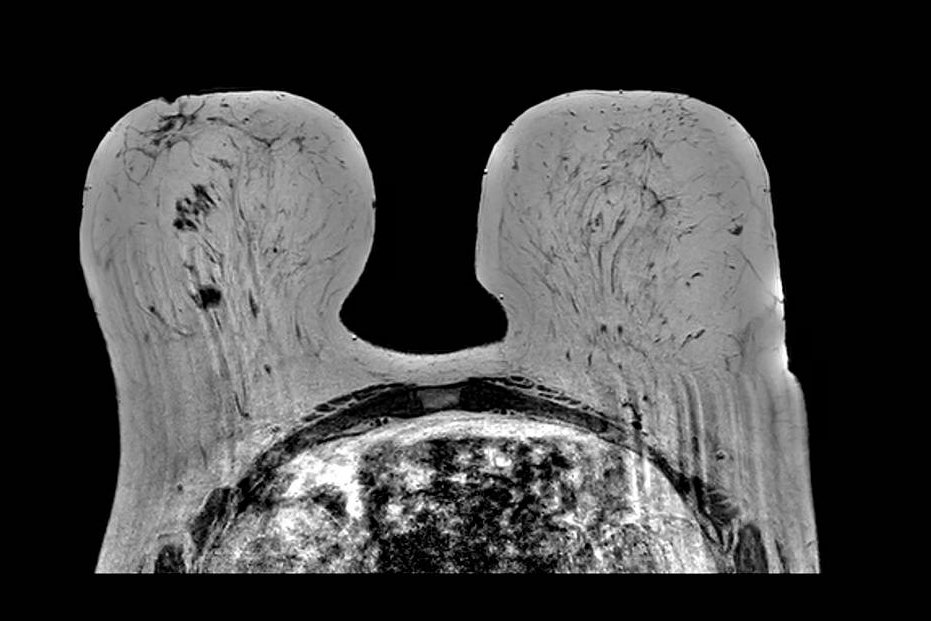

Partial Volume / Breast Fold

Partial volume artifact at a breast fold. Sagittal image shows abrupt signal change where tissue curves back on itself, creating a plane of partial volume averaging and an artifactual interface. The breast remains within the FOV; the effect reflects mixed tissue signal within single voxels at the fold. The appearance changes across adjacent slices as the fold geometry shifts through the stack.